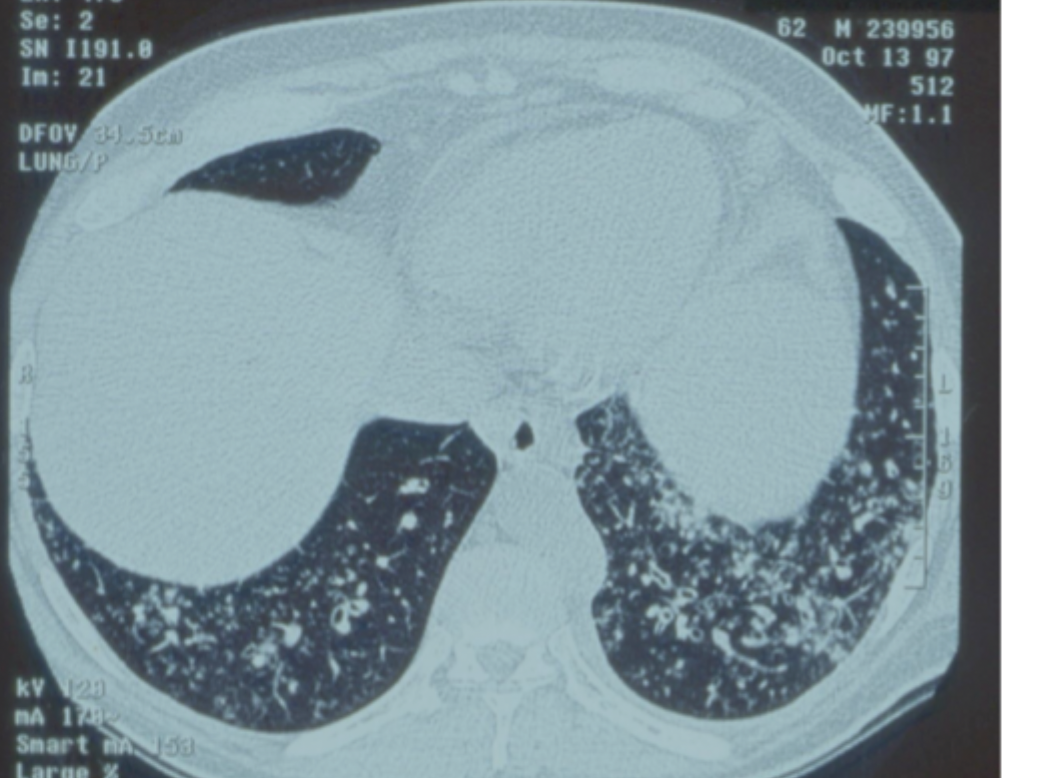

The right scan is a patient with IPF – it shows traction bronchiectasis, they have only breathlessness, no sputum, no infections, no chronic infection.

How can idiopathic pulmonary fibrosis cause bronchiecstasis ?

Traction bronchiectasis

-airway walls thicken and this pulls on and dilates airways

-only breathlessness, no sputum, no infections, no chronic infection